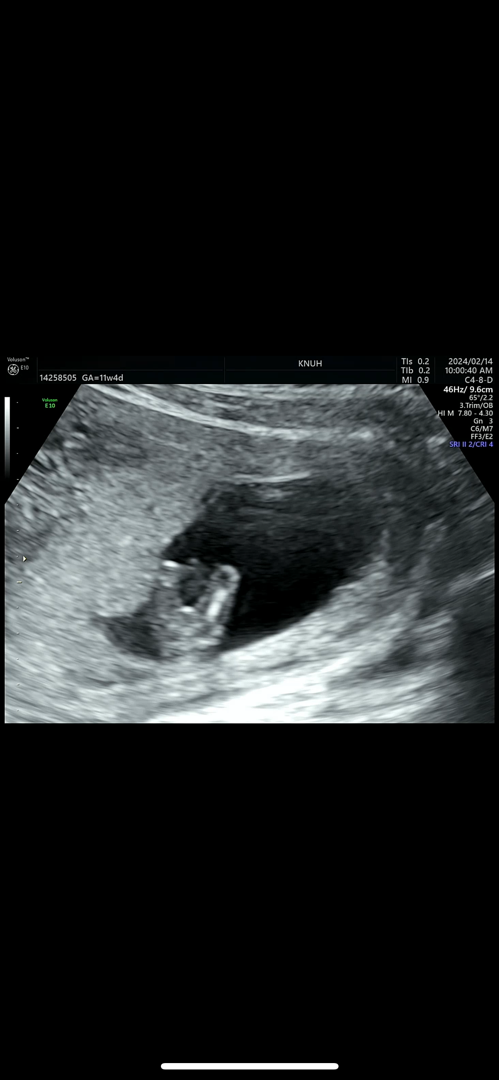

다리사이 초음파 성별 한번 봐주세요 🥹

다리사이 초음파가 정확하다길래 다시한번 올려봐요!! 편하게 참견 부탁드립니다 🥹☺️

현 사진상으로 딸같아용

의견 감사합니다 🙏